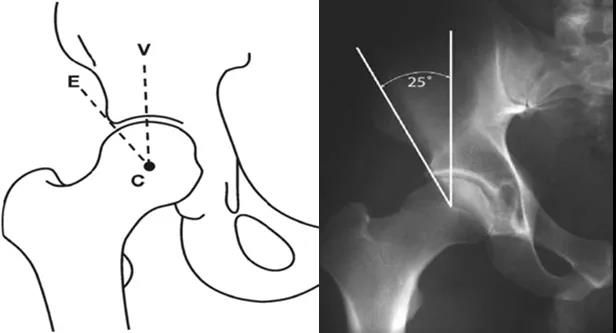

LCE角

髋关节外侧CE角(lateralcenter-edge angle,LCEA或center-edgeangle of Wiberg):根据Wiberg的描述,在骨盆前后位X线片上,C点定义为股骨头的中心,E点为髋臼最外侧处。经过C、E两点的直线与身体中线的平行线之间的夹角即为LCEA。Ogata等定义了一种新的测量方法,即取髋臼侧软骨下硬化带的外缘为E点。正常值:>25°。<20°即可诊断髋关节发育不良。但是若LCEA>45°则说明髋臼有过度覆盖的倾向。